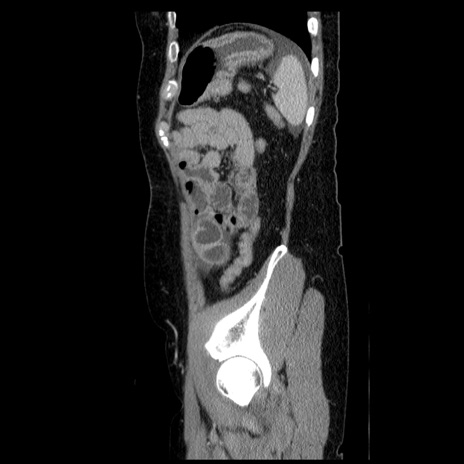

症例6(矢状断像)

【症例】50歳代女性

【主訴】下腹部痛

【現病歴】本日朝より下痢2回あり。 昼食を食べた後、嘔吐3回、下腹部痛認め、症状軽快せず、当院救急搬送。

最終食事:本日昼(生ものなし)。 昨日の夜、刺身を食ぺたとのこと。周囲に同様の症状の者なし。普段、排便は毎日あるとのこと。

【既往歴】卵巣癌術後(8年前に当院で卵巣摘出)

【身体所見】 意識清明、腹部:平坦、腸蠕動音→、やや硬、下腹部自発痛・圧痛あり、反跳痛あり、筋性防御なし。

【データ】WBC 16000、CRP 0.01